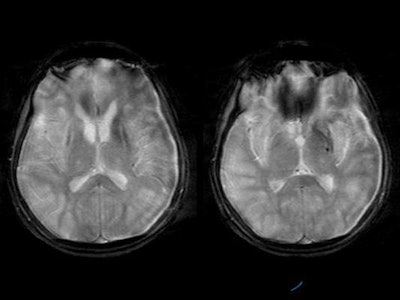

MRI was performed with the following sequences: TSE and gradient-echo T2 and FLAIR axial, TSE T2 sagittal and coronal, 3D Turboflash T1 sagittal with multiplanar reconstructions, and diffusion-weighted images with b-values of 500 and 1000 s/sq mm.

There was symmetrical hyperintensity at both putamina and thalami and the head of both caudate nuclei on T2WI and FLAIR images [Figure 1 and 2]. The thalamic lesions appear hypointense on T1WI while the putaminal lesions show mixed signal with magnetic susceptibility effects on gradient-echo images.